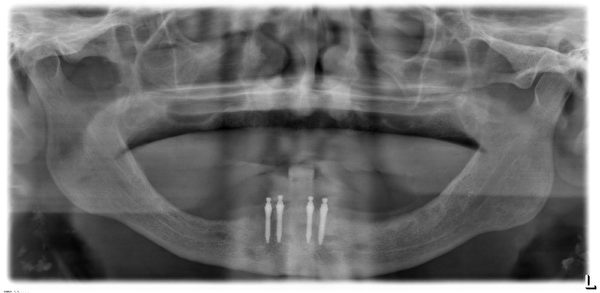

人工牙根能有效的取代缺牙,它是一种模仿牙根的钛金属,有着不同的直径、长度,医生可以依照植牙计划将其植入到患者的上颌或者下颌缺牙部位。

Mini种植体是一种直径比常规种植体小很多的特殊植体,它是用于活动义齿的修复中,要比传统的义齿修复更加稳定。

Mini种植体允许牙医不用在牙龈上切口直接植入,术后手术痛苦减少,且可以进行即刻修复

目前新加坡有两种植牙技术,一种是迷你植牙,用细小的螺丝来固定牙齿,直径只有约两毫米。

另一种是传统植牙,用的金属比较厚,植一颗牙大概要3000元到5000元,疗程也较长,一般为半年,因为有些需动手术,加强骨头支撑度后才能植牙。

相反的,迷你植牙只需几天,价格是传统植牙的一半。

迷你植牙,它是一种伤口小的微创手术。一些80岁以上的病人,不适合做传统植牙,因为骨头厚度不够,但可利用迷你植牙,帮他们植牙,改变他们的生活。

不过迷你植牙金属较薄,支撑度没有比传统植牙的金属强,长期用力可能破裂。